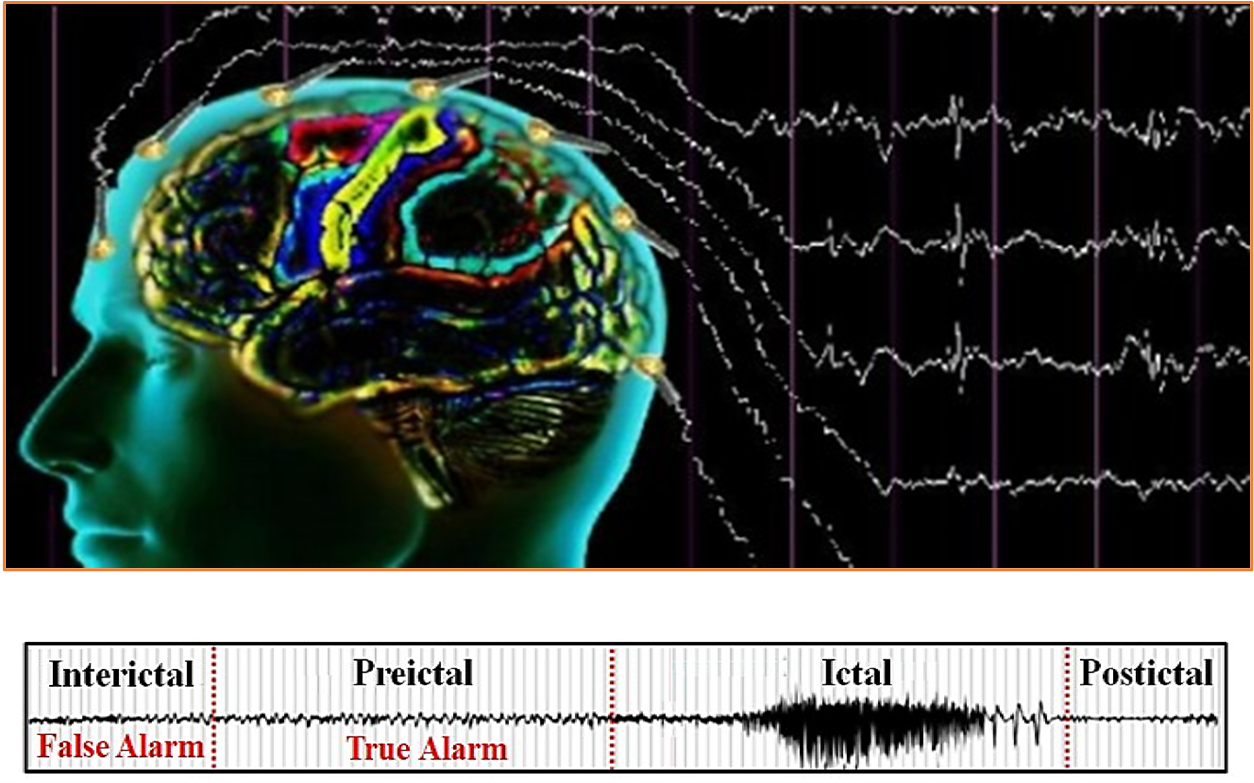

- Epileptic Seizure Prediction

By training on long-term EEG recordings, AI models now predict seizures up to one hour ahead with over 99% accuracy. Early warning systems based on these algorithms could dramatically reduce injury risk and enable timely interventions

Figure 3 Seizure prediction performance and pre ictal EEG patterns.